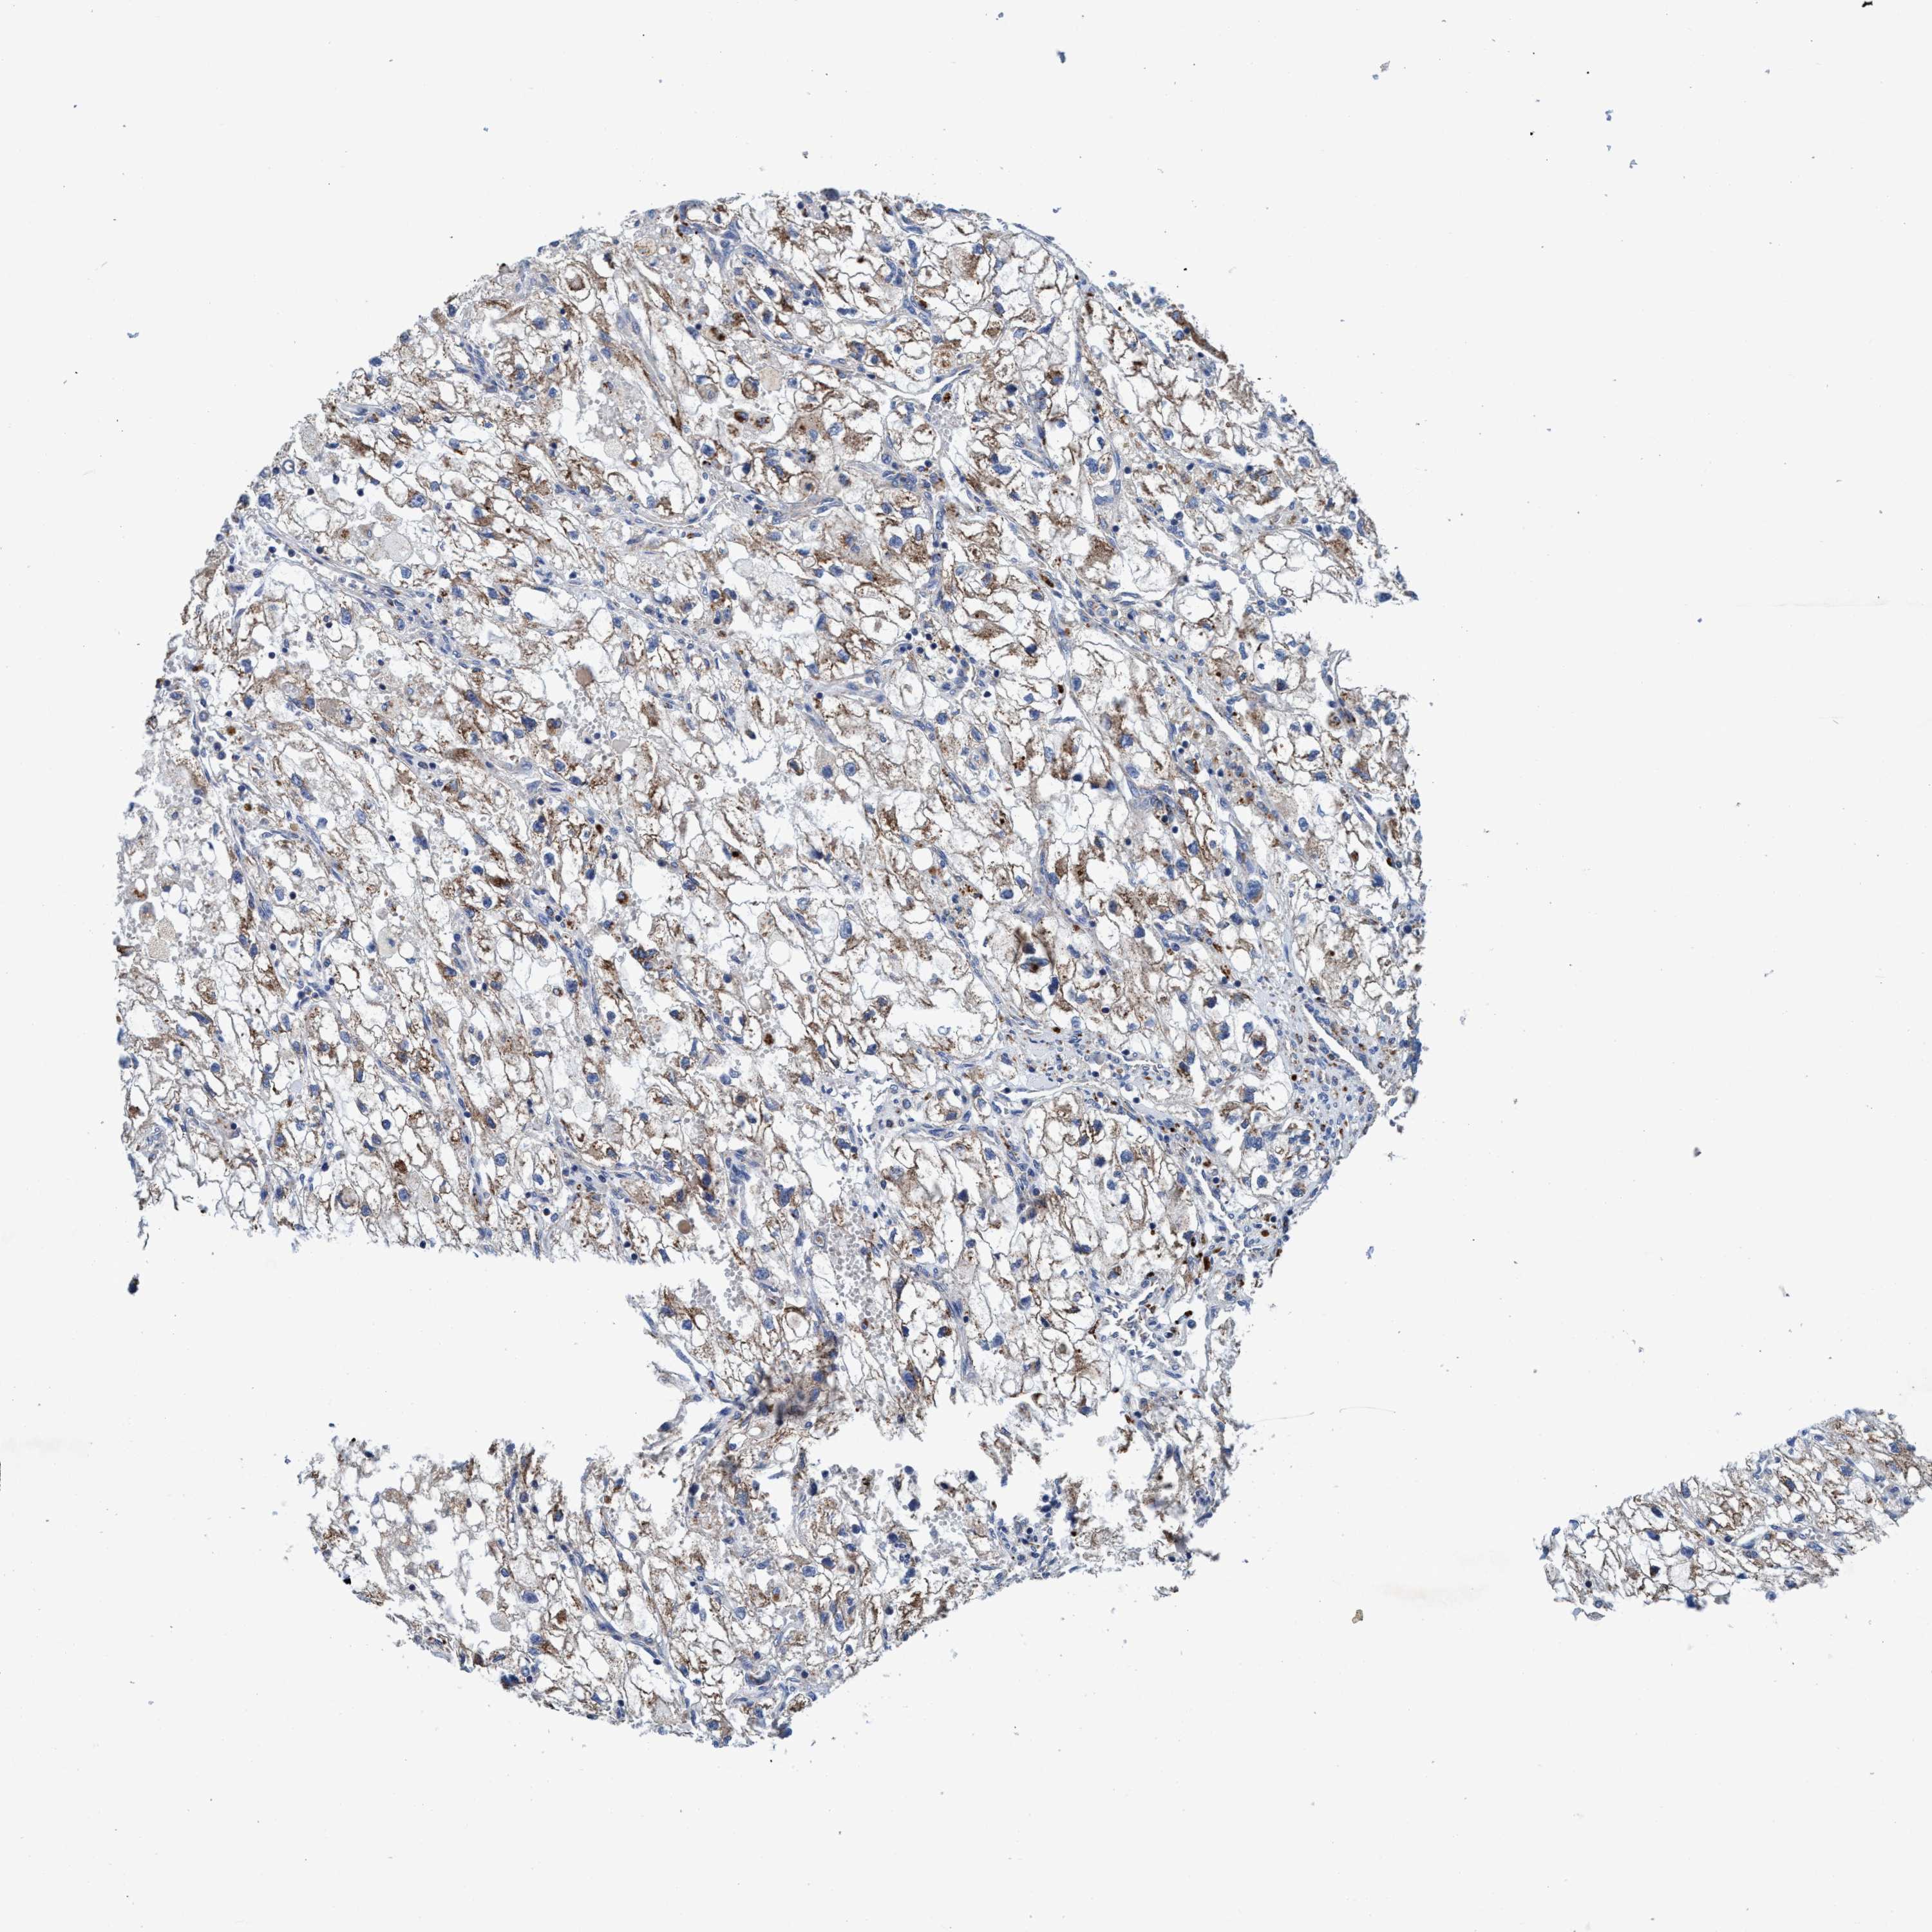

KIDNEY RENAL CLEAR CELL CARCINOMA (VALIDATION) - Interactive survival scatter ploti

ENDOG is not prognostic in Kidney Renal Clear Cell Carcinoma (validation)

: 20.69

Average pTPM 14.7

Number of samples 100